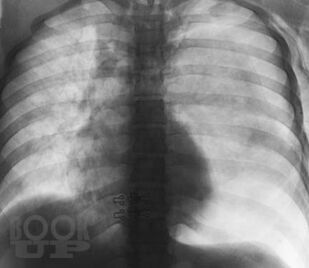

В книге изложены особенности клинической и рентгенологической диагностики повреждений и ранних осложнений закрытых травм грудной клетки. Проведен анализ объективных причин, затрудняющих основные и дополнительные методы исследования. На 240 рентгенограммах показаны признаки трудновыявляемых повреждений и осложнений травм грудной клетки, в частности пневмоторакса, гемоторакса, ателектаза, разрыва диафрагмы. Впервые отмечается клиническая значимость напряжения в малом пневмотораксе при политравме. Приведены сравнительная характеристика и алгоритм дифференциальной диагностики острых диффузных поражений легких при травме. Описан опыт выявления и решения проблемы нефункционирующего дренажа плевральной полости. Издание предназначено для хирургов, торакальных хирургов, травматологов, реаниматологов, оказывающих помощь больным с политравмой.